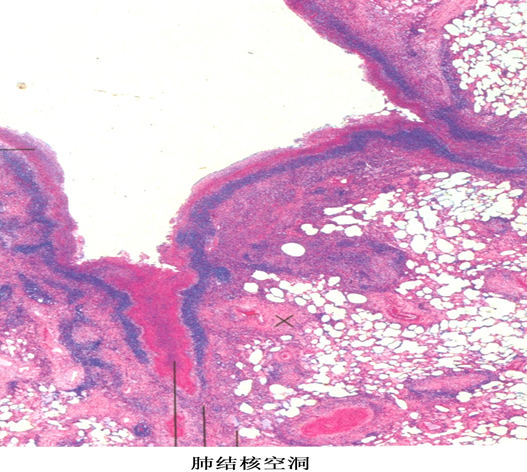

3.慢性纤维空洞型肺结核:又称开放性肺结核,是本病最主要的传染源!

①肺内有一个或多个厚壁空洞。多位于肺上叶,大小不一,不规则。

厚壁空洞病理变化:

壁厚可达1cm,镜下:镜下洞壁由内到外可分三层,内层 为干酪样坏死物(含多量结核杆菌),中层为结核性肉芽组织,外层为纤维结缔组织。

结局:经治疗,空洞可机化、闭塞或开放性愈合。